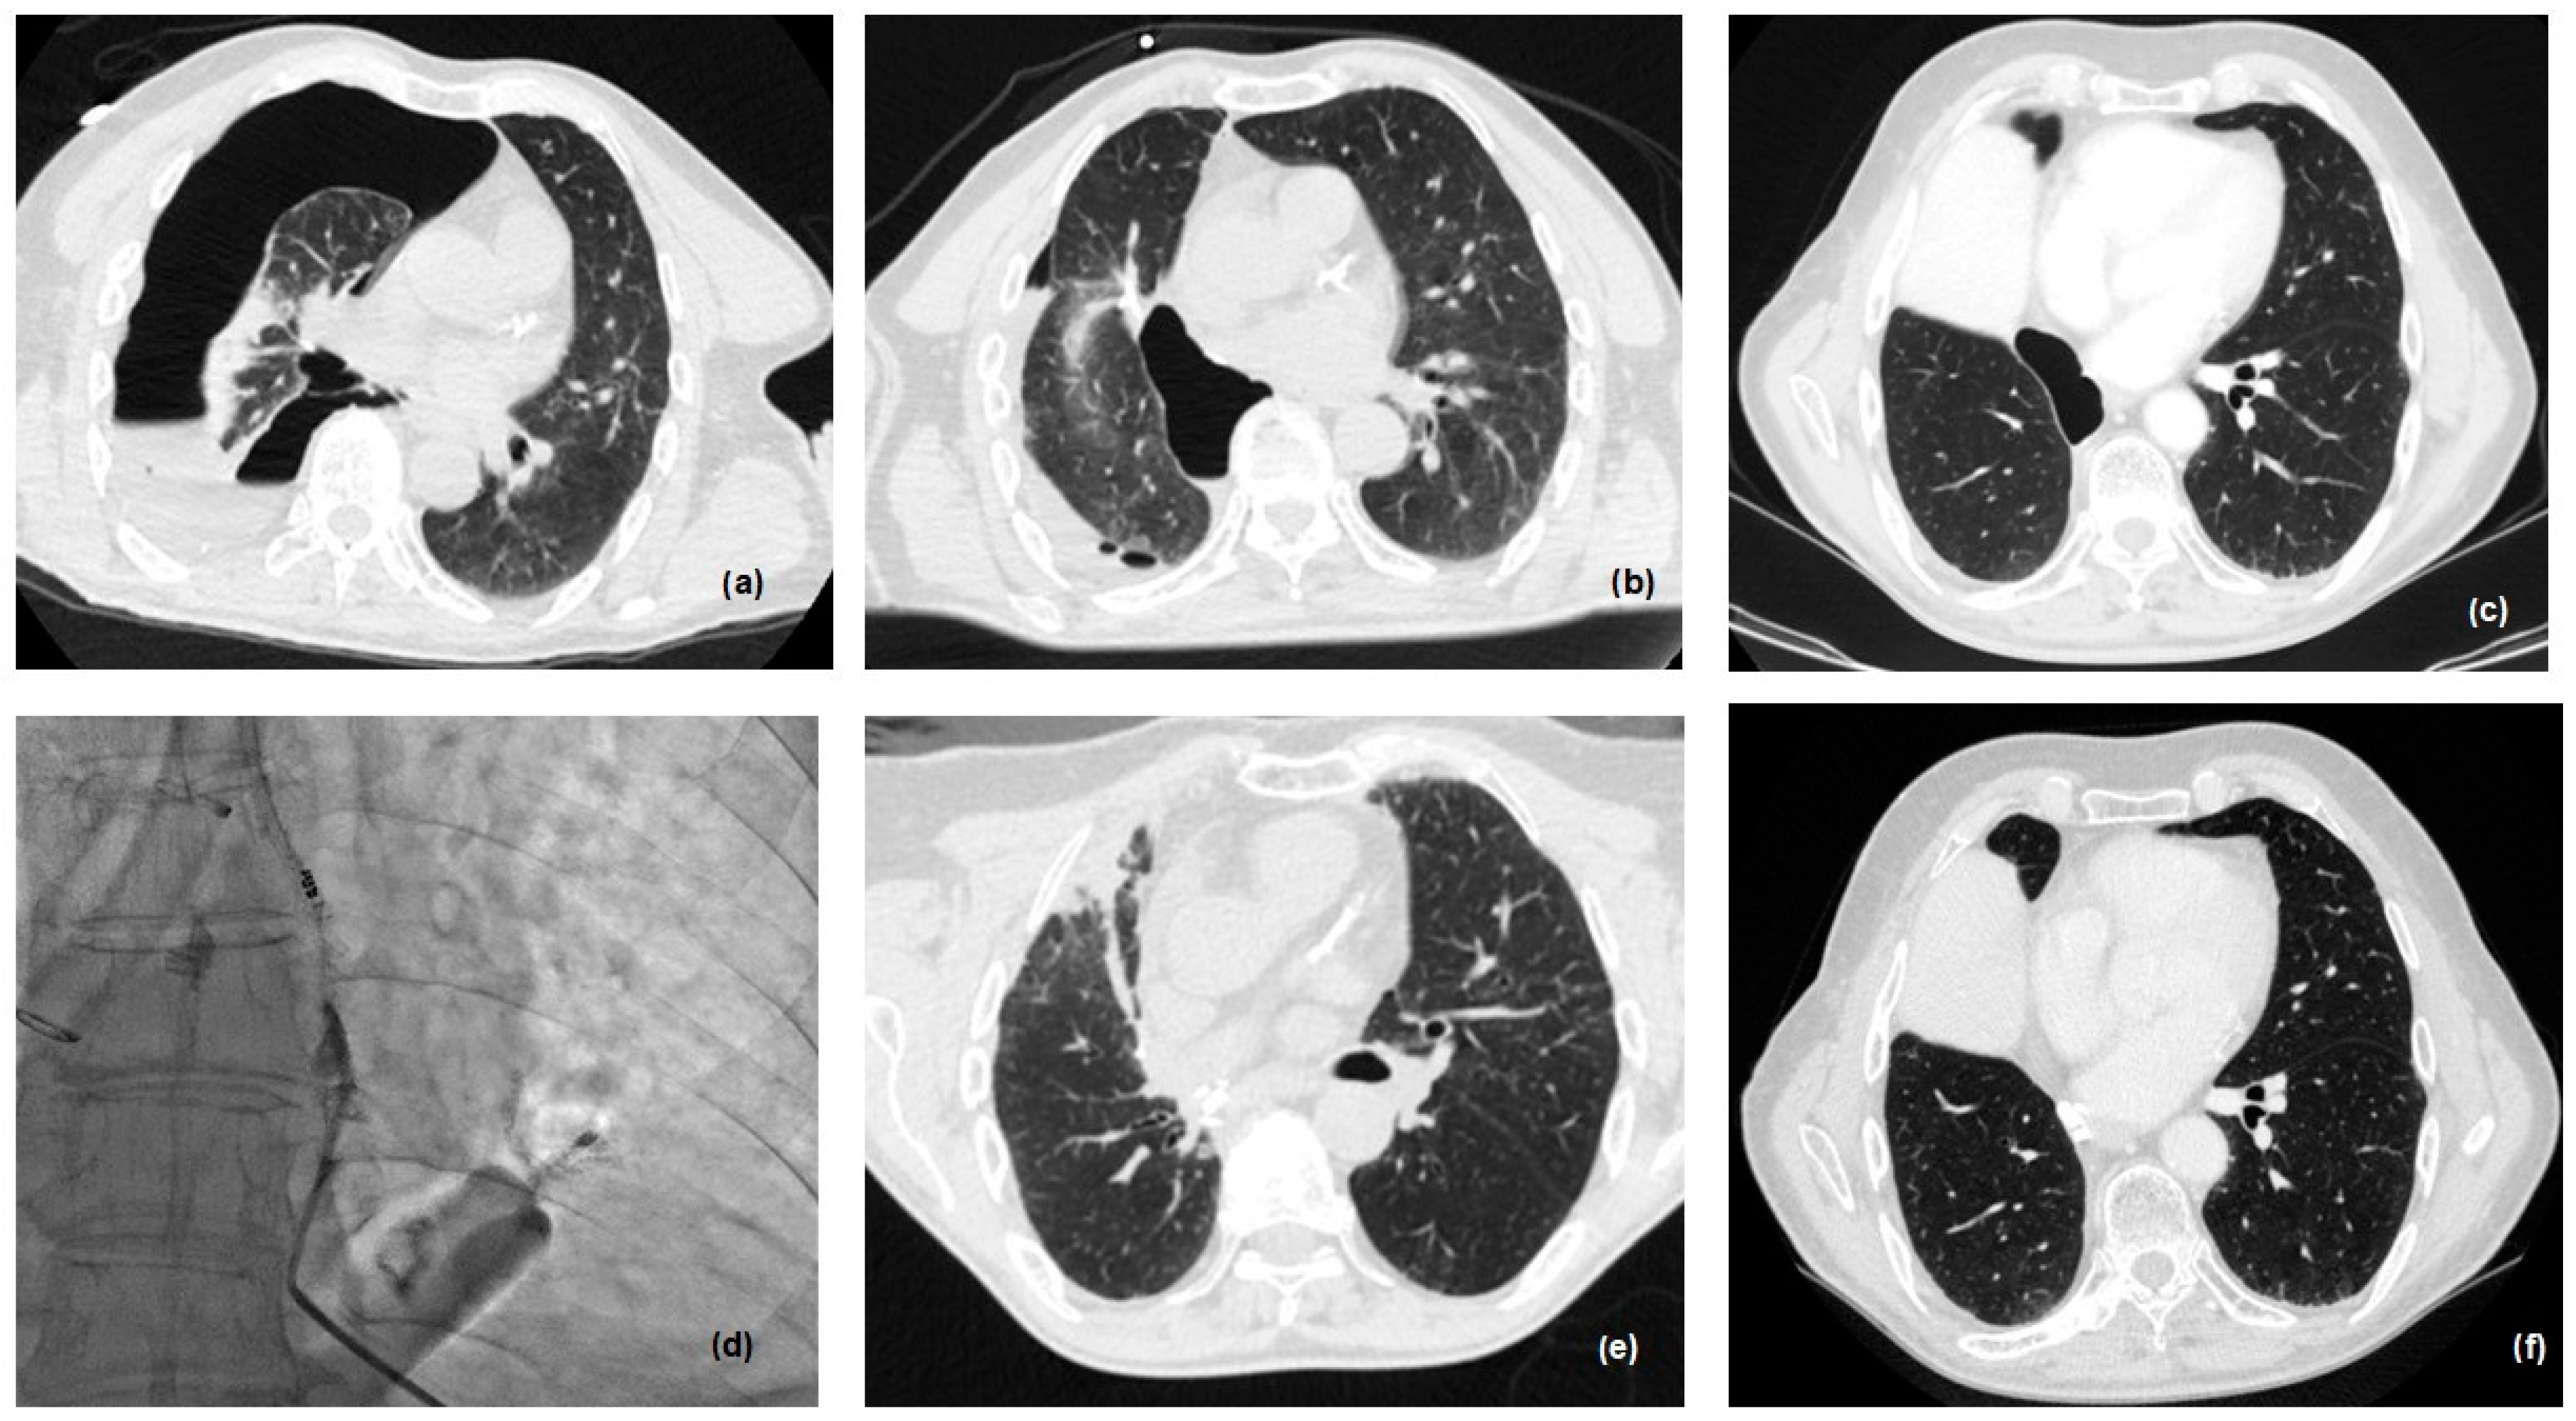

In the last 2 years, in collaboration with our team in the division of interventional radiology, we have developed a new protocol, in order to treat patients presenting with small (<0.6 cm) and late fistula (Figure 4).

Figure 4.

Percutaneous treatment of small and late BPF: (a) pneumothorax after inferior bilobectomy, 2 months after surgery; (b) drainage of pleural cavity; (c) persistence of pneumothorax after 3 months with fiberoptic diagnosis of BPF; (d) n-butyl cyanoacrylate (nBCA) glue injection under CT guidance, via 22-gauge Chiba needle into the postulated site of air leak/BPF; (e) immediate post-procedure CT scan control; (f) CT scan after 6 months.

Indeed, percutaneous treatment of BPF after lobectomy is usually attempted in patients who are unfit or not eligible for surgery or bronchoscopic interventions, or in the case of the failure of the less invasive surgical treatment before proceeding with main surgery [21].

The treatment of discrete and visible fistulae is usually performed using an n-butyl cyanoacrylate (nBCA) glue injection under CT guidance. After percutaneous pleural drainage, a 20/22-gauge Chiba needle is inserted percutaneously under CT or fluoroscopic CT guidance into the postulated site of air leak and the nBCA glue mixture is subsequently injected directly into the BPF (Figure 4). The ratio of nBCA to Lipiodol in the mixture and the total amount of glue mixture injected may vary based on the size of the fistula and proceduralist preferences, (ranging in the literature from 1:3 to 4:1 and 0.2 mL to 6 mL). The use of synthetic hydrogel surgical sealant has also been described, with results similar to glue [22].

In the last 2 years, we introduced a new method for treating BPF, in collaboration with the division of interventional radiology. In two cases, BPF was closed by percutaneous injection of an nBCA glue mixture. The success rate in these two patients was 100%.

A final aspect to take into consideration, and which we are evaluating more and more recently, is represented by the hybrid closing percutaneous approach to the fistula. In some selected cases, a simple intervention radiology procedure, via general anesthesia, allows the closure of the BPF with the use of glue and butyl-cyanoacrylate, under CT guidance. These are preliminary data (only two patients) but the success rate is complete, avoiding all post-operative problems for the patients.

It is obvious that it is a method that will have to be validated over time with further observations and evaluations, but at the moment could represent a keystone in the mini-invasive treatment of BPF.